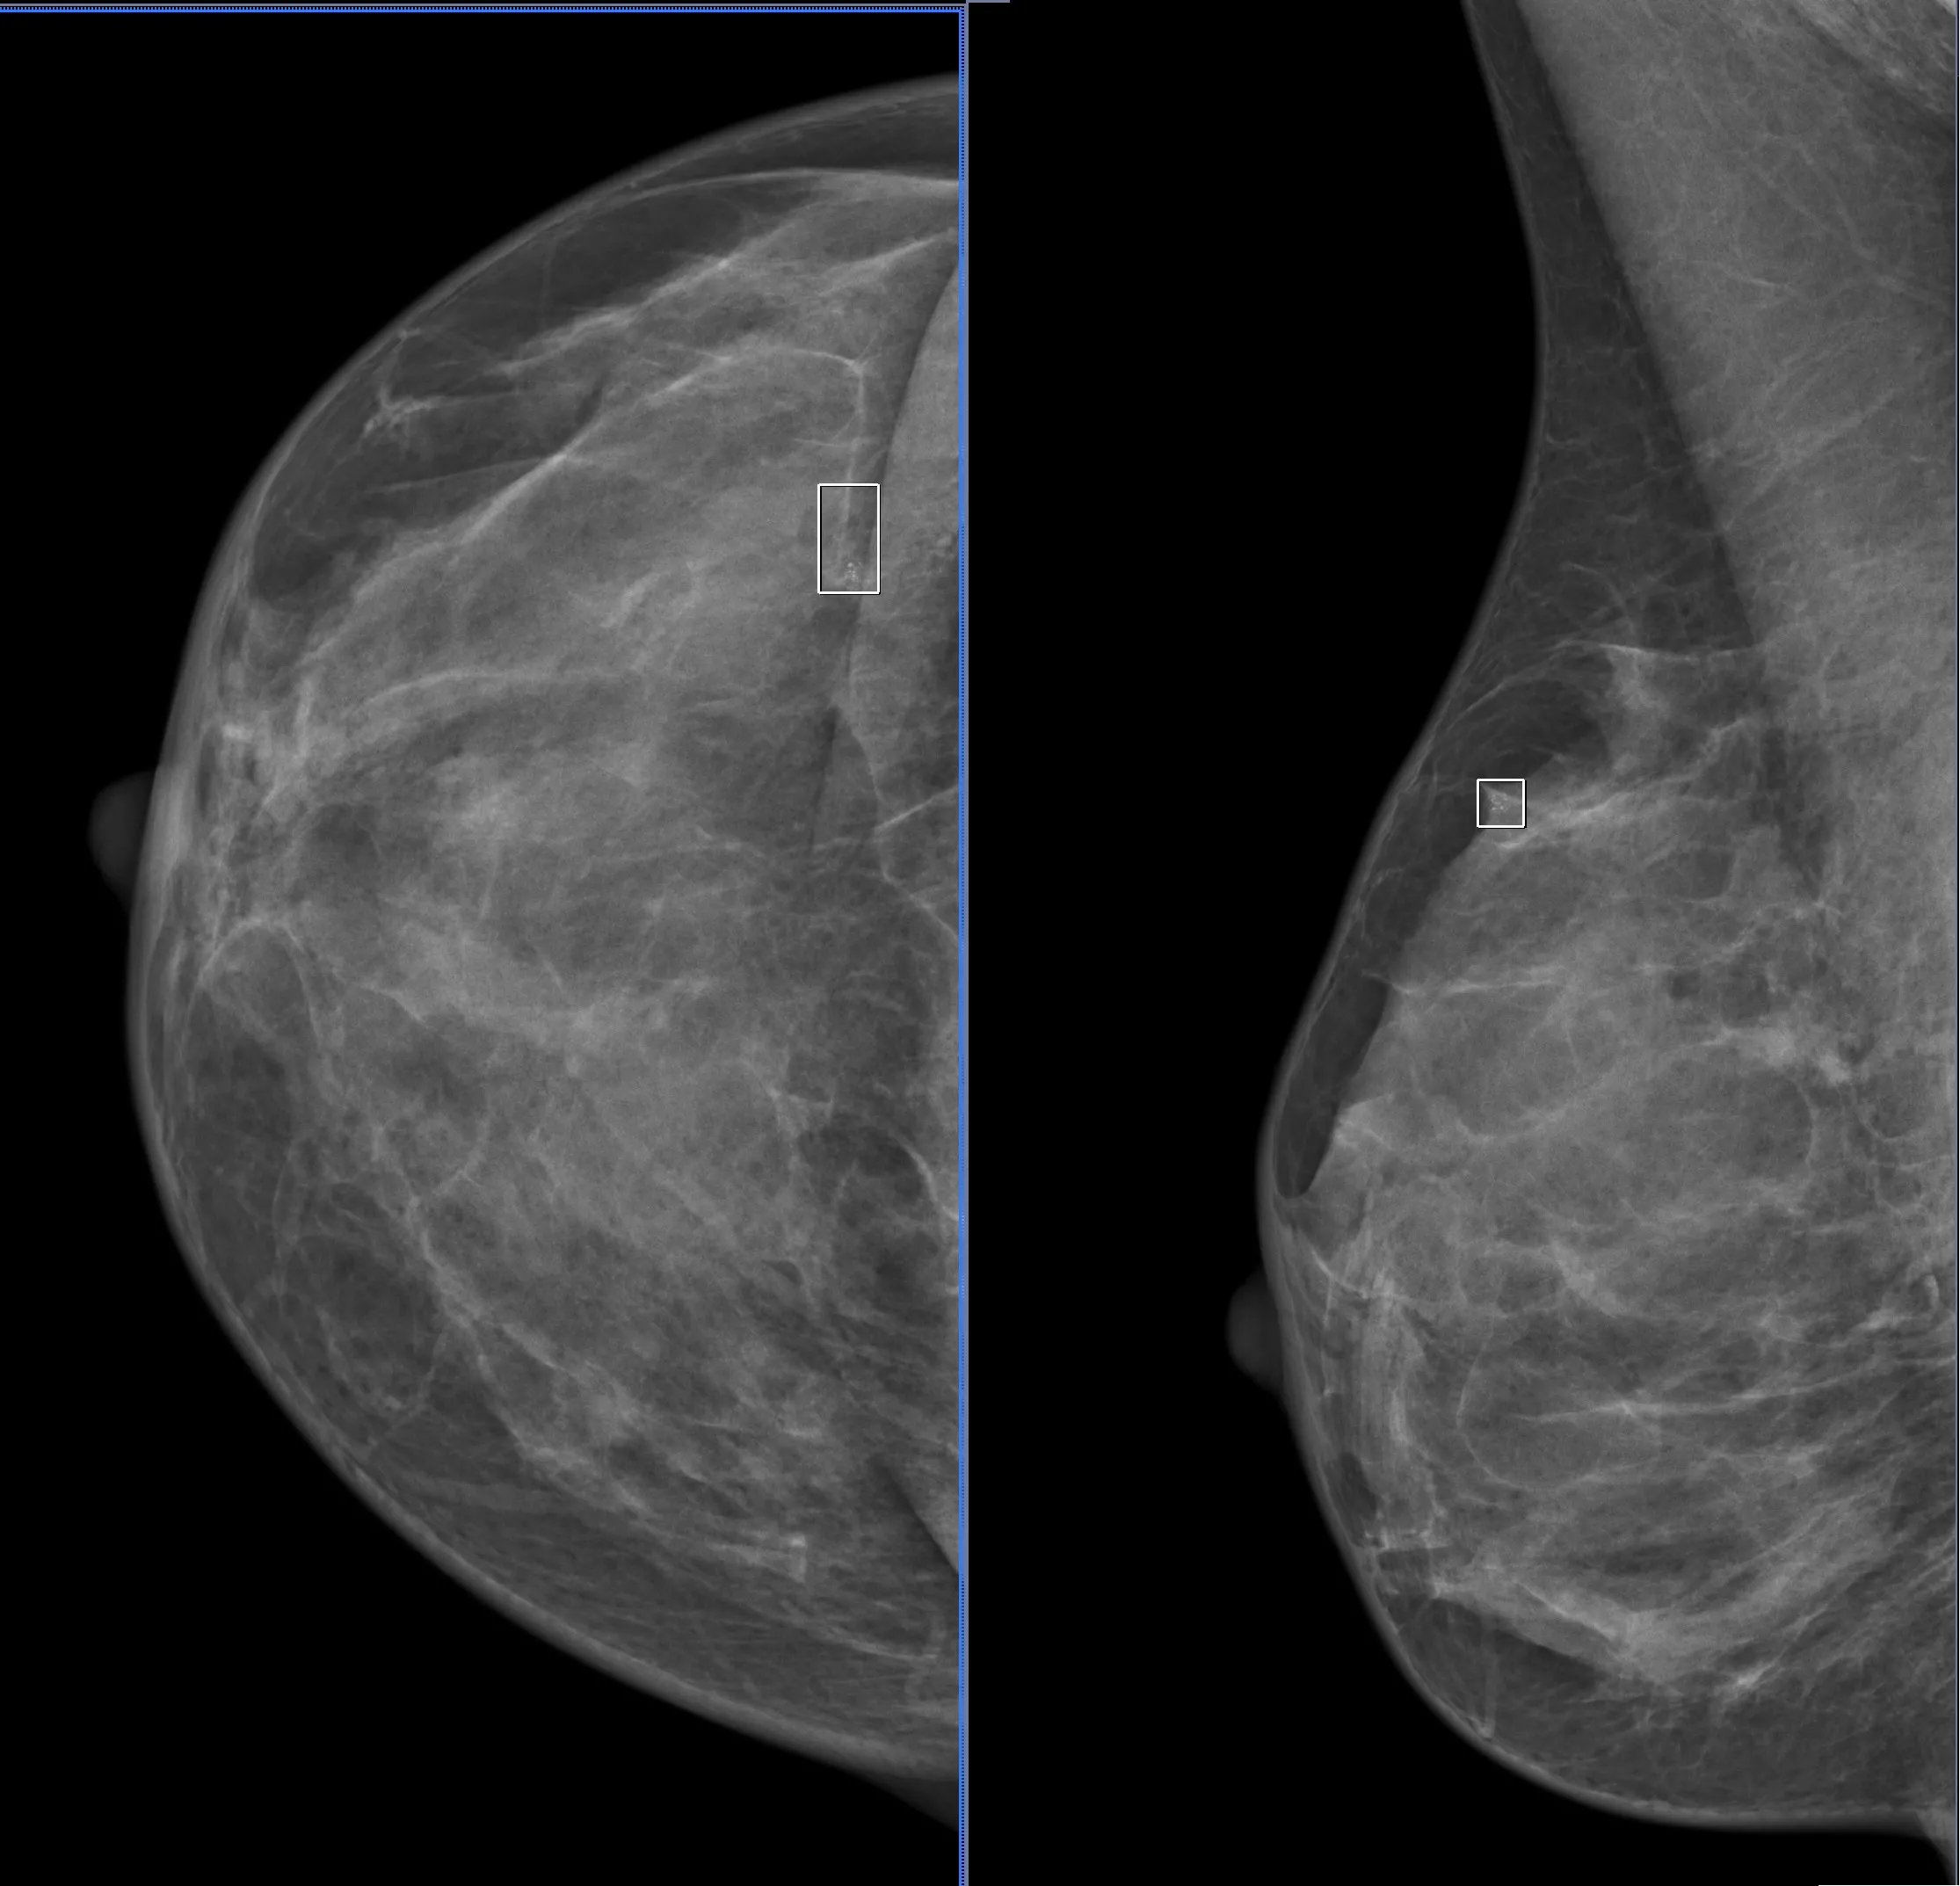

Ранее, во времена радикального, но не онкопластического подхода при лечении рака молочной железы, в таких случаях выполняли мастэктомию. Этой пациентке врач-маммолог, онкопластический хирург Оксана Васильевна Шулига-Недайхлебова первым этапом лечения предложила плановое оперативное вмешательство в объеме онкопластической лампэктомии правой МЗ с интраоперационным гистологическим исследованием чистоты краев резекции, биопсией сторожевых лимфоузлов. Учитывая специфичность образования, на предоперационном этапе breast-радиологом была установлена метка-локалайзер (фото) в участок микрокальцинатов под контролем маммографии.

Интраоперационно был выполнен рентгенконтроль удаленного сектора МЗ. Рентгенография интраоперационного материала установила, что патологически измененная ткань полностью удалена. Но в целях двойного и надежного контроля материал также отправлен на срочное (экспресс) морфологическое исследование чистоты краев резекции после цветовой маркировки. В заключении интраоперационного гистологического исследования рентгенологически данные радикального удаления опухоли подтверждены. Проведено дополнительное иссечение краев резекции и отправлено на экспресс морфологическое исследование – пока не получен результат чистых краев резекции дважды.

Финально маммографические размеры опухоли – 3 мм, гистологические – 6 мм. Это первая, ранняя стадия, рак in situ, промежуточной степени злокачественности, тип ER+++, PR+++, Her-2/neu+, который имеет хороший прогноз дальнейшей жизни пациентки. Индекс Ki-67 низкий, что также, как биомаркер пролиферации, подтверждает надежду на выздоровление от рака МЗ.